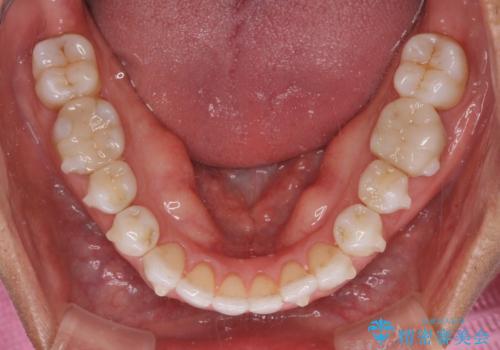

- 治療途中の前歯と上下前歯のデコボコ気にして来院された患者様です。

前歯のデコボコはインビザラインにより歯列を整え、その後に、前歯などをオーダーメイドタイプのオールセラミッククラウンにて補綴治療することとしました。

長時間のマウスピース装着に協力いただき、短期間で歯列をしっかりと改善することができました。

ホームホワイトニングを併用していただいたので、とても明るい口元に仕上がり、患者様には大変満足していただきました。